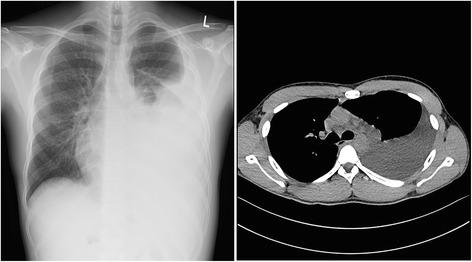

A chest X-ray and computed tomography (CT) scan revealed massive left-sided pleural effusion (Fig. 1). A complete blood count revealed hemoglobin of 13.8 g/dL; total leukocyte count, 17.7 × 103/mm3 with predominant neutrophils (77%); and a platelet count of 238 × 103/mm3. The blood biochemistry profile was as follows: protein, 4.4 g/dL; albumin, 2.1 g/dL, cholesterol, 223 mg/dL; glucose, 92 mg/dL; lactic dehydrogenase (LDH), 190 U/L; alkaline phosphatase, 46 IU/L; aspartate aminotransferase, 16 IU/L; alanine aminotransferase, 20 IU/L; blood urea nitrogen, 18.1 mg/dL; and creatinine, 0.85 mg/dL. His C-reactive protein level was 3.9 mg/L. A microurinalysis revealed 3+ protein and 2+ blood on a dipstick and 10–19 red blood cells/high-power field. The spot urine protein/creatinine ratio was 4.7.

Fig. 1.

Chest PA and chest CT showing left-sided pleural effusion